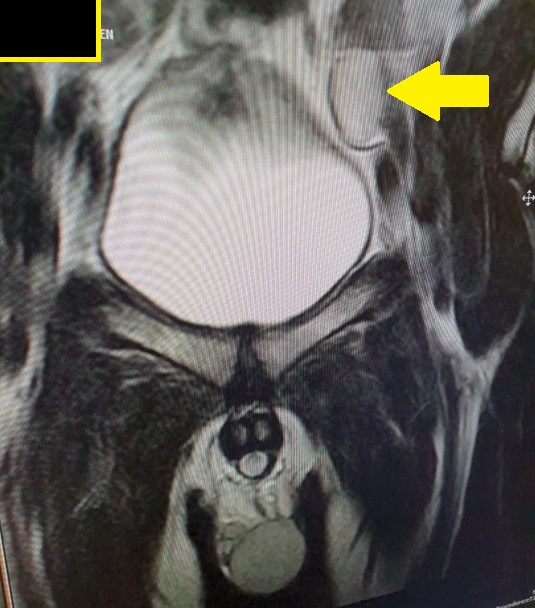

From www.indianradiology.com

Undescended Testes MRI Sumer's Radiology Blog What Is A Undescended Testicle Operation If the testicles don't descend by 6. The testicles begin developing in male babies before they’re born, and normally drop. An orchiopexy also typically describes the surgery. Undescended testicles will usually move down into the scrotum naturally by the time your child is 3 to 6 months old. What is undescended testicle repair surgery (orchiopexy)? What is an undescended testicle. What Is A Undescended Testicle Operation.

From radiopaedia.org

Undescended testes Image What Is A Undescended Testicle Operation There are usually no other. What is an undescended testicle repair? Undescended testicles will usually move down into the scrotum naturally by the time your child is 3 to 6 months old. An orchiopexy is a surgery that moves an undescended testicle into the scrotum. If the testicles don't descend by 6. An undescended testicle, sometimes called a cryptorchidism testicle,. What Is A Undescended Testicle Operation.